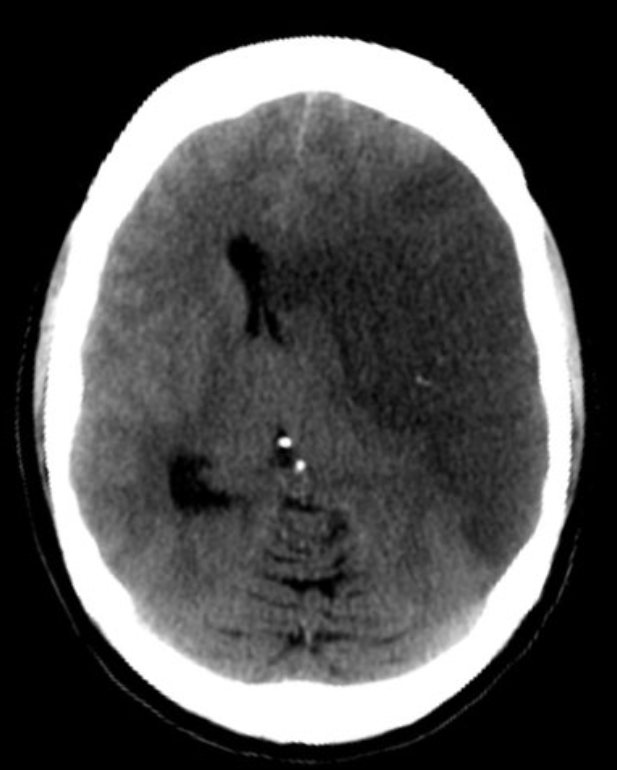

Tomografia de crânio com a área escura extensa de AVC isquêmico por oclusão de grande vaso (lado direito da figura), que não recebeu tratamento com trombectomia.